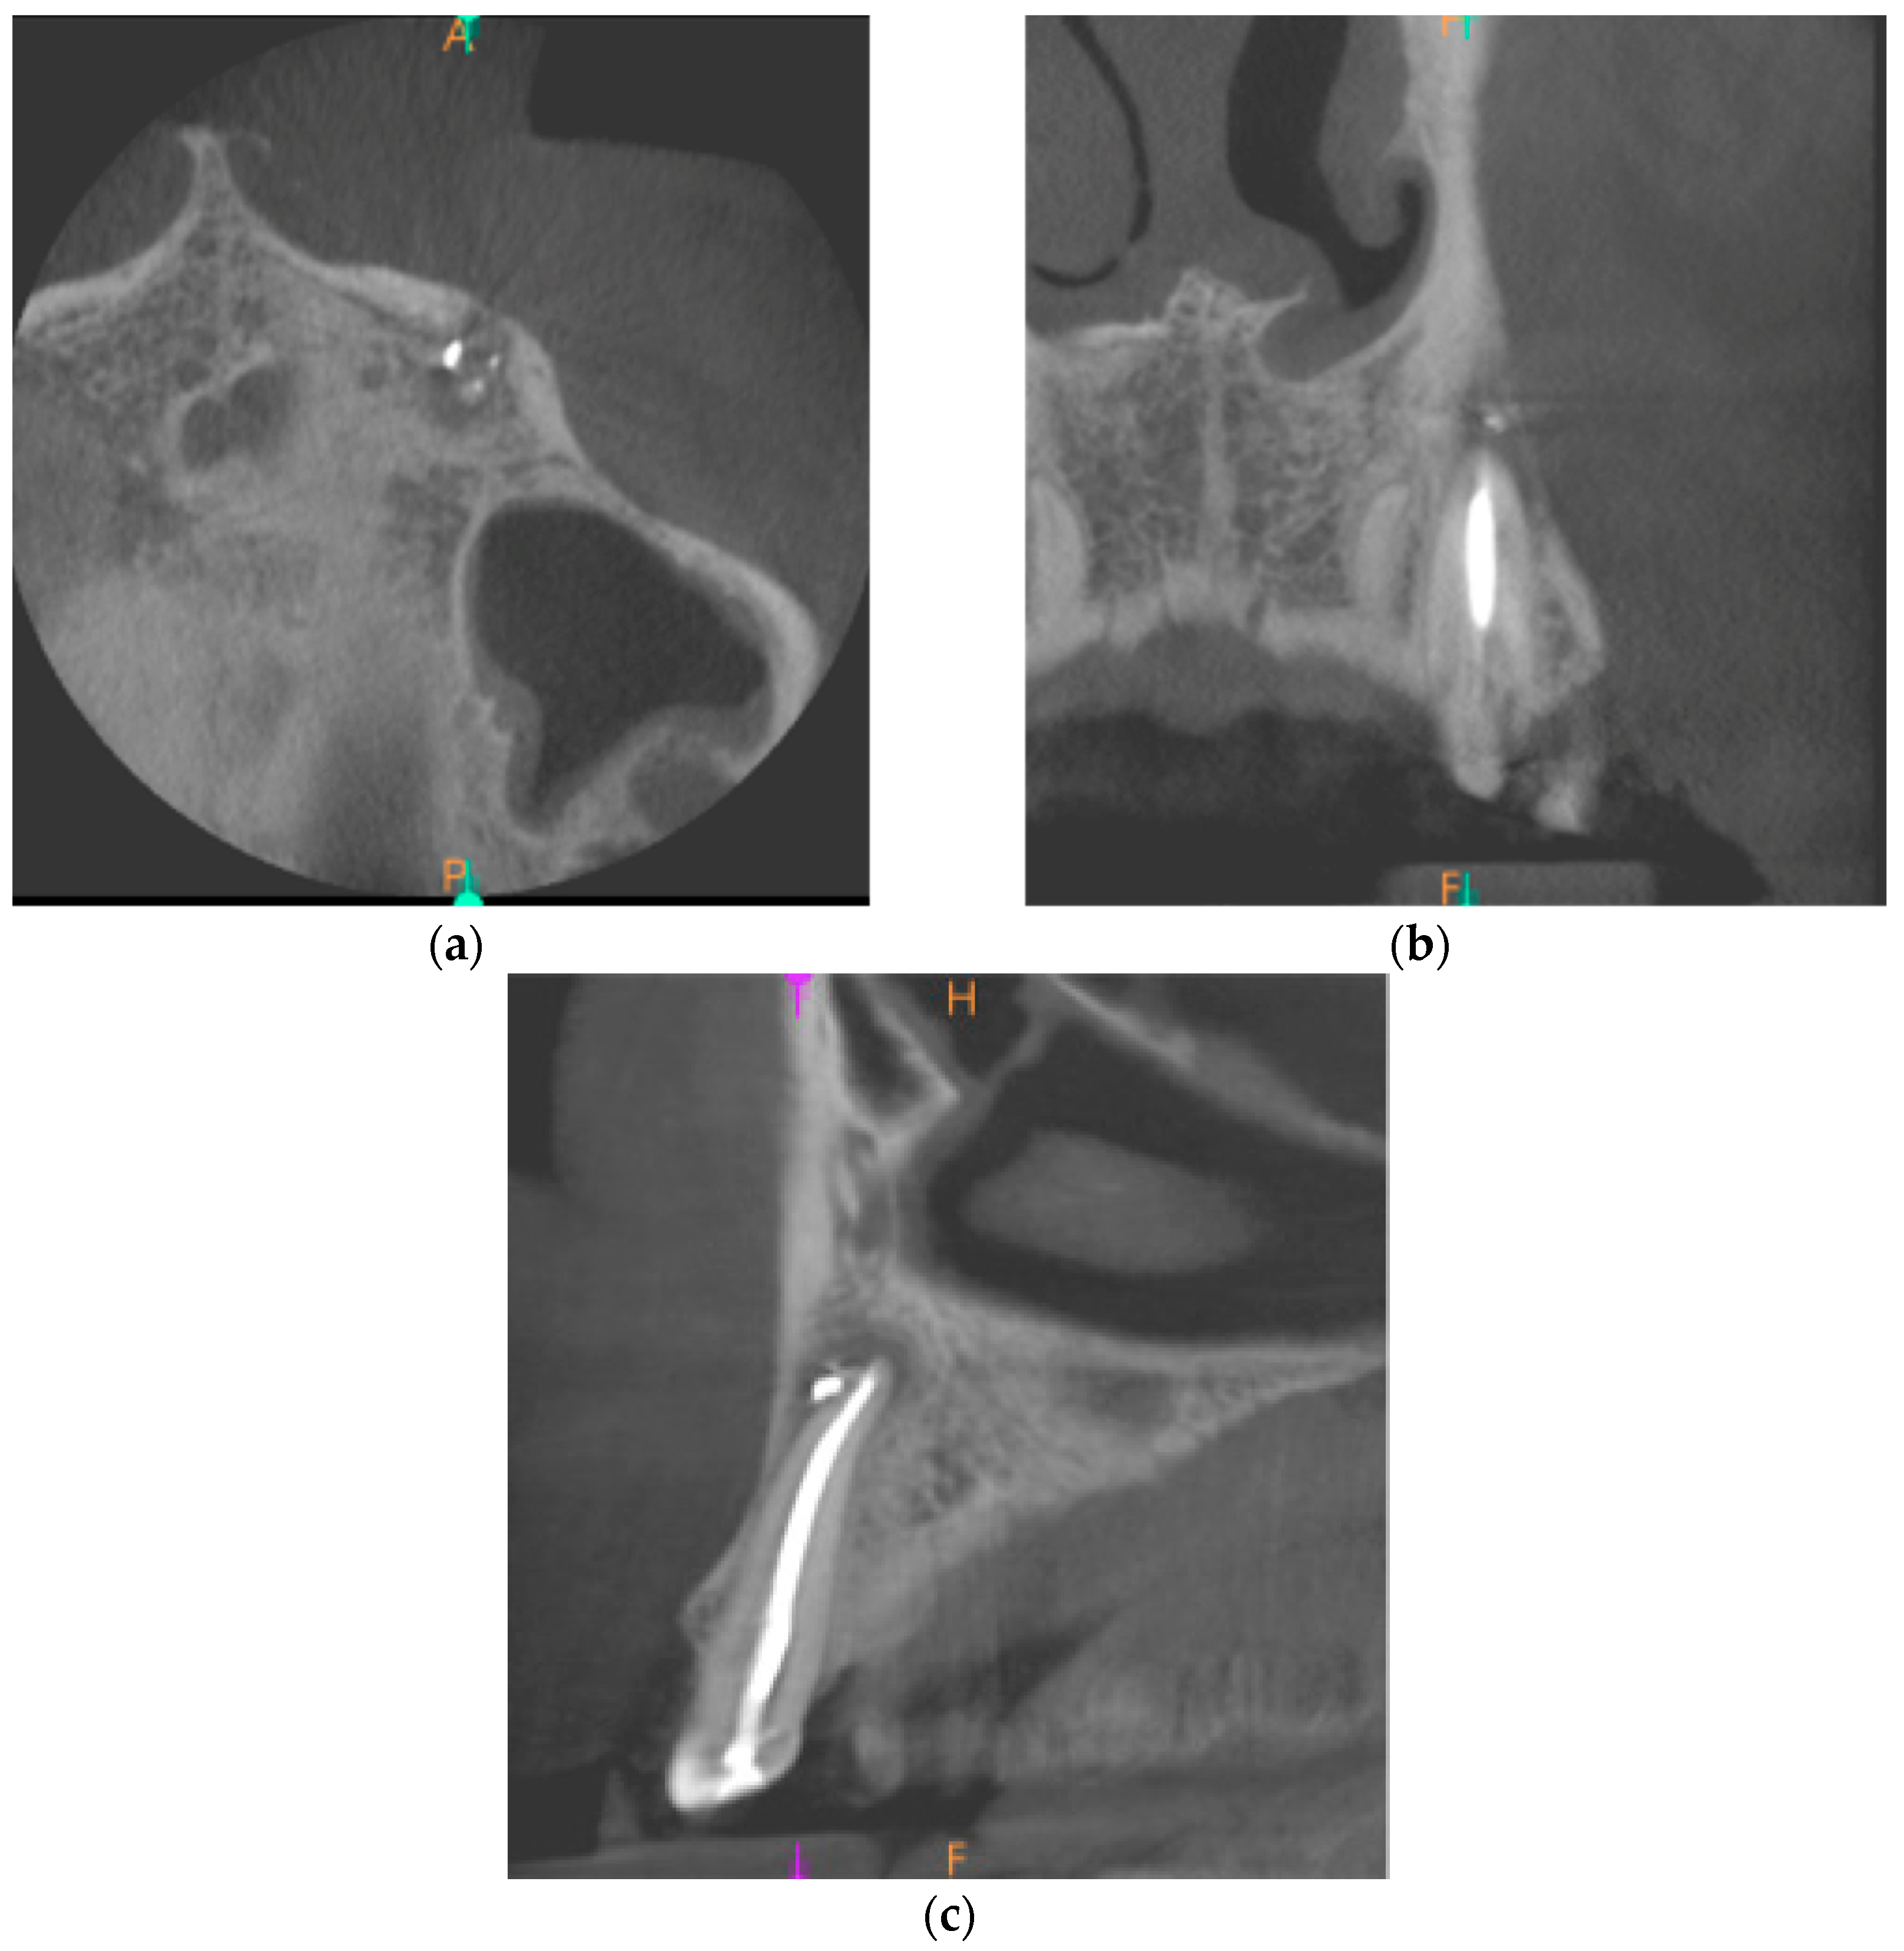

Finally, 5 months after the end of the treatment, there was no evidence of any pathological symptoms. The CBCT images revealed the process of healing of the periapical lesion. There was a small area of radiolucency around tooth no. 23 with the reduced dimensions of 4.6 × 4.6 × 2.1 mm. Figure 6 presents the CBCT images of the healing process of the periapical lesion 5 months after the end of endodontic treatment.

Figure 6. CBCT images presenting the healing process of the periapical lesion around the root of tooth no. 23 (date of CBCT examination: 29 June 2021): (a) axial view; (b) coronal view; and (c) sagittal view.